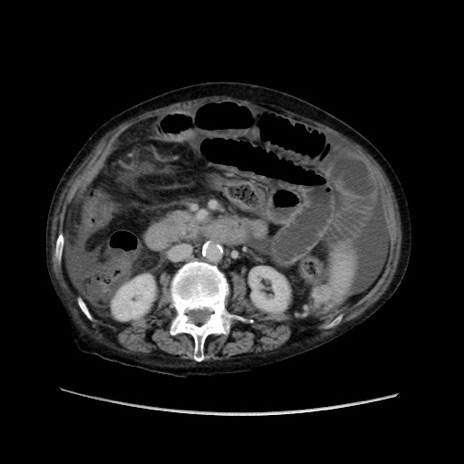

症例31(横断像)

【症例】80歳代 女性

【主訴】腹部膨満感

【現病歴】他院にて肝硬変にてフォロー中。1週間前から便秘、腹部膨満感、臍部腫瘤あり受診となる。

【既往歴】肝硬変

【身体所見】腹部膨隆あり、皮膚変化なし、疼痛なし。

【データ】WBC 4600、CRP 0.25